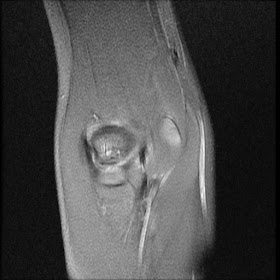

Capitellar OCD